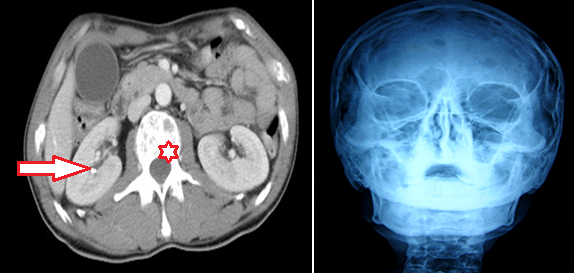

Les pancréatites aigues restent majoritairement d'origine biliaire dans notre contexte. Les autres étiologies sont rarement identifiées et la pancréatite est le plus souvent classée « idiopathique ». Nous rapportons un cas de pancréatite aigue révélant un myélome multiple, en insistant sur l'intérêt des paramètres biologiques et de l'imagerie dans l'orientation diagnostique. Notre patient est âgé de 45 ans, ayant des antécédents de coliques néphrétiques épisodiques non documentées, a été admis pour des épigastralgies transfixantes évoluant depuis 3 jours dans un contexte d'apyrexie. A l'examen clinique, le patient présentait une sensibilité épigastrique isolée. Le bilan biologique objectivait une hyperlipasémie à 17 fois la normale. Le scanner abdominal objectivait une pancréatite stade C: pancréas augmenté de taille avec infiltration de la graisse péri-pancréatique. Par ailleurs, on note de multiples lésions ostéolytiques vertébrales et une lithiase calicielle droite (A). Les explorations biologiques montrent une hypercalcémie à 123 mg/l, une insuffisance rénale à 22 ml/min de clearance de créatinine. Le dosage de PTH était par ailleurs normal. Un traitement d'urgence de cette hypercalcémie majeure a été instauré à base d'une hyper-hydratation intraveineuse associée à la corticothérapie. Une radio du crane de face avait mis en évidence de multiples lésions ostéolytiques à « l'emporte pièces ». L'association de telles lésions ostéolytiques oriente l'enquête étiologique de l'hypercalcémie vers un mécanisme de déminéralisation osseuse. L'électrophorèse des protéines urinaires avait identifié une protéinurie de Bences jones. L'immunofixation des protéines plasmatiques et urinaires avait mis en évidence la présence d'une gammapathie monoclonale à chaine légère type kappa. Le myélogramme a révélé une infiltration plasmocytaire à 35% confirmant le diagnostic de myélome multiple. Une chimiothérapie a été alors démarrée.